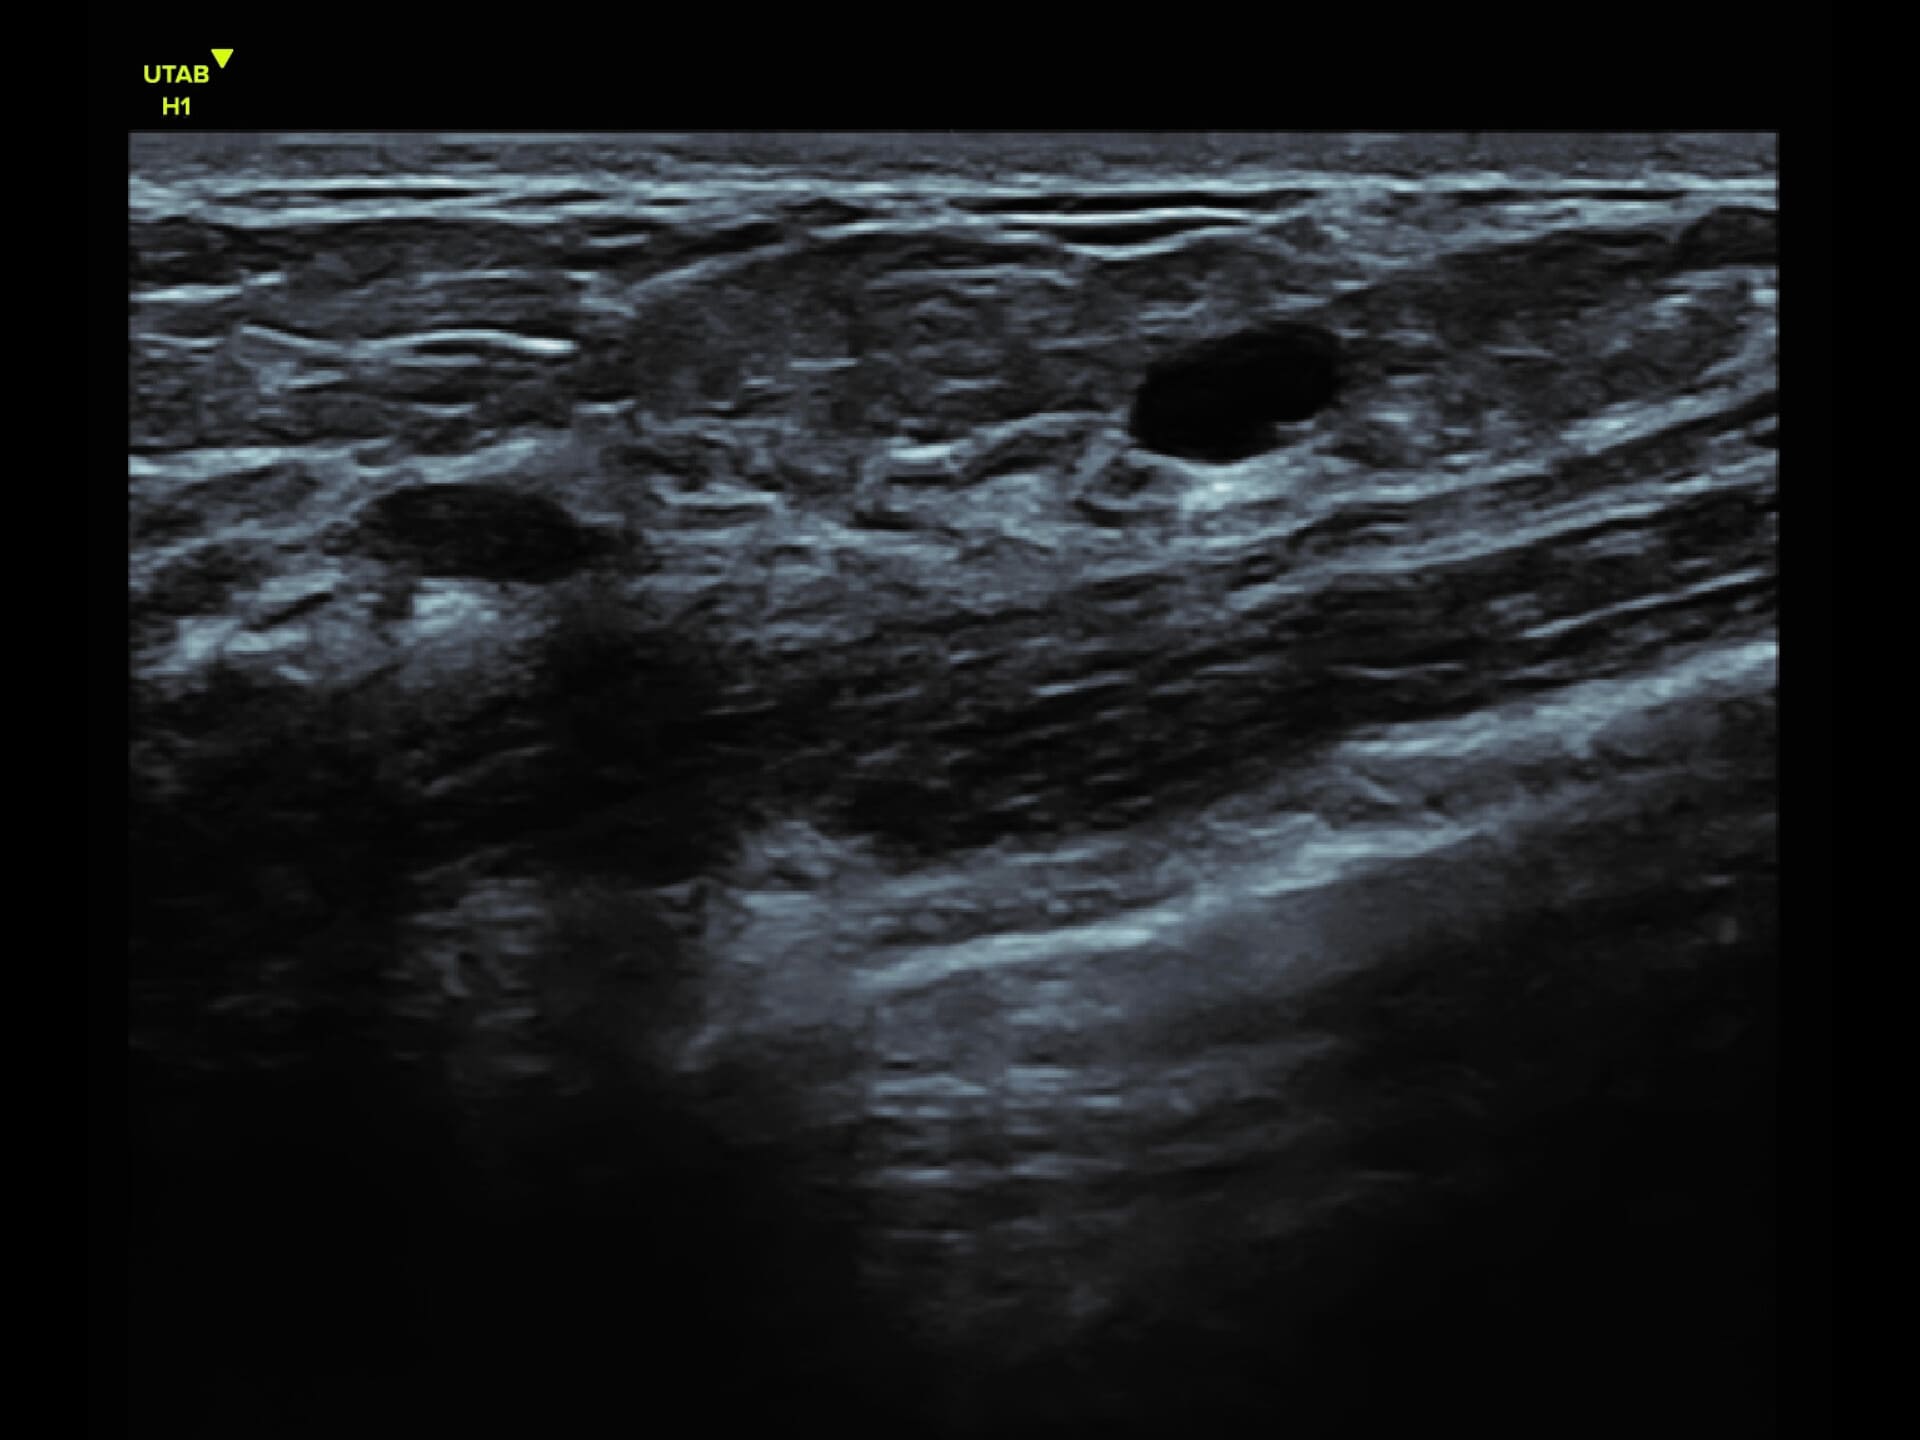

L9-2 Linear Array Probe

Crystal-clear imaging for muscles, vessels, and soft tissues—perfect for targeted exams and real-time procedures.

The L9 – 2 is a linear array ultrasound probe featuring advanced wideband technology, which enables a broader frequency range for superior image resolution and clarity. This enhanced imaging capability makes it ideal for a range of clinical applications.

The L9 – 2 is a linear array ultrasound probe featuring advanced wideband technology, which enables a broader frequency range for superior image resolution and clarity.

This enhanced imaging capability makes it ideal for a range of clinical applications.

Applications:

Musculoskeletal, Thyroid, Small Parts, Pediatrics, Peripheral Vascular, Breast, Obstetrics

B-mode, HI, XBeam, Speckle Reduction, Virtual Convex, M-mode, PW (Update, Duplex, Triplex, HPRF), CFM, PD